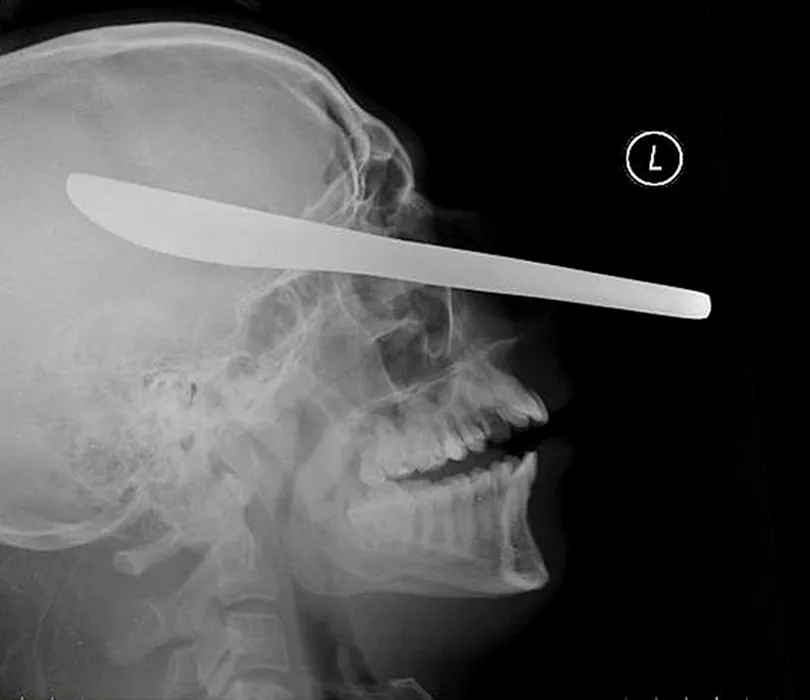

GALERIE FOTO: Cele mai terifiante radiografii